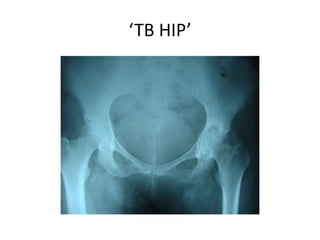

‘TB HIP’

EPIDEMOLOGY

• Bones and joints and affected in ~5% of pts

with TB

• Commonest is spinal TB in ~50% of cases

• Hip – 15% of all osteoarticular TB

• Can occur in any age group but is more

common in children.

• Next common after spinal TB